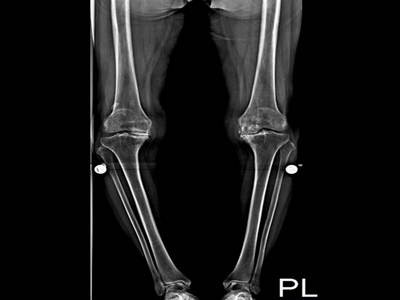

孫女士於六月底抵達花蓮慈院,經由x光檢查報告,確定孫女士的雙膝蓋嚴重磨損。陳英和表示,一般膝蓋在健康情況下,頂端會呈現圓弧狀,但孫女士的則已磨平,加上退化性關節炎長久下來,會導致關節變形,原本腳型正常的人就有可能變成O型腿,孫女士的雙腿已經呈現向外彎曲約二十度。

圖:術前術後x光報告比對圖。左圖為術前,健康膝蓋頂端會呈現圓弧狀,孫女士的則已嚴重磨損、磨平,且雙腿呈現向外彎曲約二十度O型腿狀;右圖為孫女士接受「微創式人工膝關節置換手術」後的雙膝狀況。